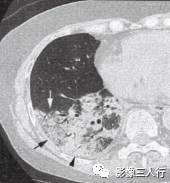

胸部CT图像显示,在含气少的致密肺的背景上见到含气的支气管,表现为两种形态: ①在大片肺实变病灶内的细条状空气密度影;②直径Imm的小泡状空气密度影,连续的几 个层面都能出现(图2、图3)。该征象表明:①近侧气道通畅;②肺泡内的空气经吸收(肺不张)或取代(肺炎、肺癌),或两者综合而消失。通畅含气的支气管在肺泡实变高 密度区内表现为管腔内低密度充气轮廓。